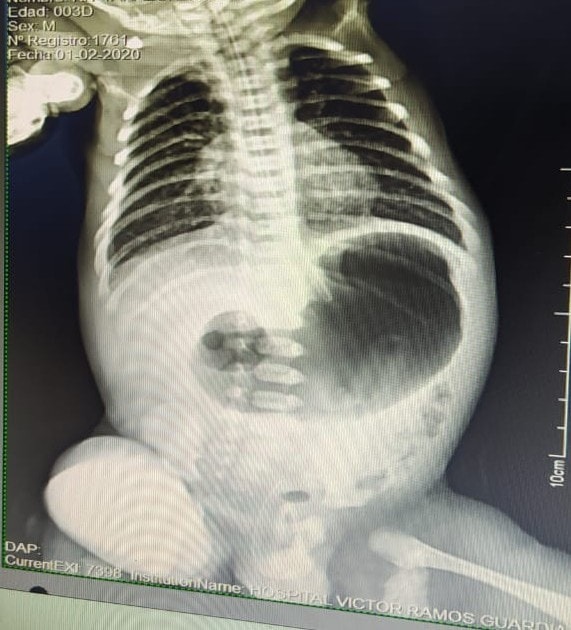

Un recién nacido, con dos kilos de peso, mediante laparascopía fue intervenido exitosamente al presentar una atresia duodenal (malformación que genera que el bebé nazca con un segmento del intestino cerrado o bloqueado en uno o más sectores, dejando un espacio).

La intervención fue realizada por el Dr. Jorge Romero Soriano – Cirujano pediátrico del hospital Víctor Ramos Guardia de Huaraz, junto a un equipo de profesionales de la salud, como un anestesiólogo, una enfermera y una técnica en enfermería.